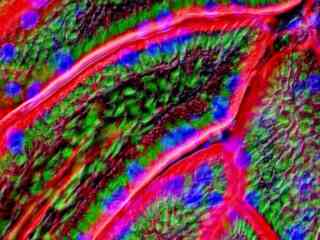

Fluorescence Microscopy

The widefield reflected light fluorescence microscope has been a fundamental tool for the examination of fluorescently labeled cells and tissues since the introduction of the dichromatic mirror in the late 1940s. Furthermore, advances in synthetic fluorophore design coupled to the vast array of commercially available primary and secondary antibodies have provided the biologist with a powerful arsenal in which to probe the minute structural details of living organisms with this technique. In the late twentieth century, the discovery and directed mutagenesis of fluorescent proteins added to the cadre of tools and created an avenue for scientists to probe the dynamics of living cells in culture. This gallery examines the fluorescence microscopy of both cells and tissues with a wide spectrum of fluorescent probes.

Rat Sections

The humble rat has had an outsized impact on human history. In the Middle Ages, the black rat (Rattus rattus) was blamed for spreading the Black Plague through its fleas, a pandemic that killed a third of Europe's population, an estimated 34 million people. In modern times, however, a larger cousin, the Brown rat (Rattus norvegicus) has become an important model organism in biological research. Selective breeding of the Brown Rat has produced the albino laboratory rat. Rats grow quickly to sexual maturity and are easy to keep and breed in captivity.